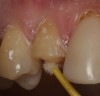

If using a three-step, total-etch technique, then the previously described steps should be followed. In the case of a one-step, self-etch adhesive, a slight variation to the previously described technique can be used. The steps of applying the one-step, self-etch are exactly the same. For example, after completing the tooth preparation on a maxillary right lateral where the patient had recurrent decay around the existing restoration margin (Figure 11), activated Brush&Bond was applied for 20 seconds (Figure 12). An air-water syringe was used to remove the excess adhesive and evaporate the solvents and water (Figure 13) and then light-polymerized for 10 seconds.

Figure 11 After completing the tooth preparation on a maxillary right lateral where the patient had recurrent decay around the existing restoration margin, activated Brush&Bond was applied for 20 seconds. An air-water syringe was used to remove the excess adhesive and evaporate the solvents and water and then light-polymerized for 10 seconds.

Figure 11

Figure 12   After completing the tooth preparation on a maxillary right lateral where the patient had recurrent decay around the existing restoration margin, activated Brush&Bond was applied for 20 seconds. An air-water syringe was used to remove the excess adhesive and evaporate the solvents and water and then light-polymerized for 10 seconds.

Figure 12

Figure 13  After completing the tooth preparation on a maxillary right lateral where the patient had recurrent decay around the existing restoration margin, activated Brush&Bond was applied for 20 seconds. An air-water syringe was used to remove the excess adhesive and evaporate the solvents and water and then light-polymerized for 10 seconds.

Figure 13